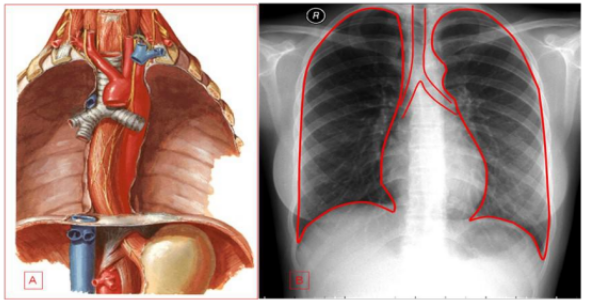

A compreensão da anatomia torácica é fundamental para a interpretação adequada das imagens de TC.

Órgãos principais da respiração, divididos em lobos (3 no direito, 2 no esquerdo)

Via aérea principal que se bifurca nos brônquios principais

Região de entrada e saída de estruturas vasculares e brônquios

Espaço entre os pulmões contendo coração, grandes vasos, esôfago e traqueia

Visão geral da anatomia torácica (Fonte: Wikimedia Commons)